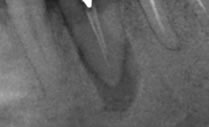

朝日歯科クリニックでは大谷エンドドンティックス方式の東洋化学 オブチュレーションシステムを用いて垂直加圧根菅充填を行っています。

院長は歯科医師になってからずっとこの術式で根管治療を行っています。予後が良いとされるこの根菅充填を勉強したい方は是非お問い合わせください。

側枝

近心に側枝があります 。オブチュレーションなら側枝まできれいに根菅充填できます。

RCF

根尖まできれいに充填されています。